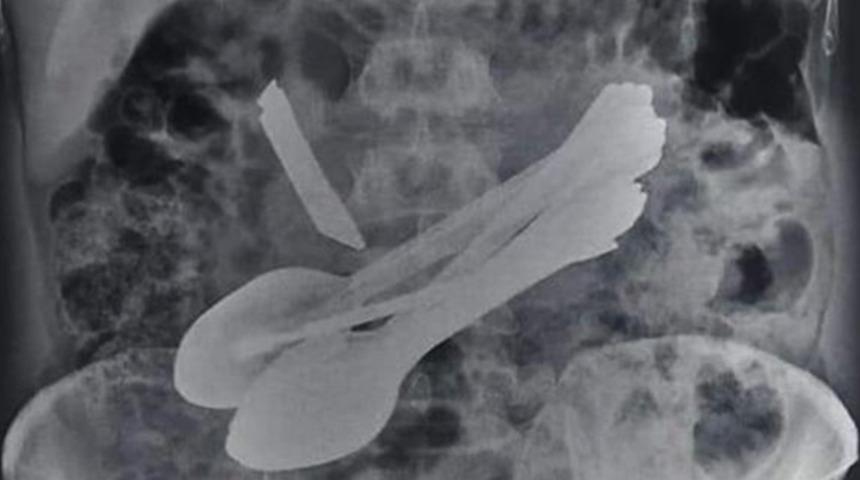

Hindistan’da karın ağrısı şikâyetiyle hastaneye giden 35 yaşındaki akıl hastası bir adamın karnından kaşık, kapı kilidi, tornavida ve diş fırçası çıkarıldı.

Doktorun ameliyat sırasında adamın karnında bir tornavida bulmasından sonra, 35 yaşındaki adam New Chowk kentindeki Shri Lal Bahadur Shastri Devlet Hastanesi'ne sevk edildi. Burada yapılan muayenede X-Ray ve röntgen sonuçları adamın karnında birkaç yabancı maddenin bulunduğunu göstardi. Bunun üzerine burada tekrar ameliyata alından adamın karnından 8 kaşık, 2 tornavida, 2 diş fırçası, bir mutfak bıçağı ve bir kapı kilidi çıkarıldı.